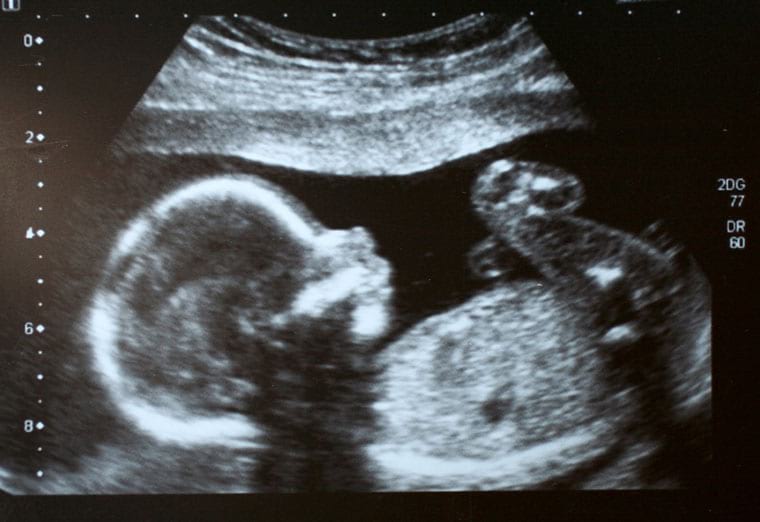

עבור נאווה חן, התובעת, היה הריון זה הריון שני ואת מעקב ההיריון היא ביצעה אצל רופא מטעם קופת חולים כללית. בסקירת מערכות מוקדמת, שנערכה בשבוע ה-15 להיריון, נצפו בצווארו של העובר ציסטות די צדדיות בגודל 3 מ"מ והתובעת הופנתה לרופא המטפל, ד"ר ערבה, לשם המשך בירור. ממנו הופנתה לייעוץ גנטי ובין ההמלצות שקיבלה לאחר מכן היתה ביצוע סקירת מערכות מאוחרת מורחבת. ממצאי בדיקה זו, שנערכה בשבוע ה-22 להיריון ונערכה במסגרת קופת החולים, היו תקינים. התובעת התמידה במעקב ההיריון שכלל בדיקות שגרתיות אצל הרופא המטפל ובדיקות אולטרסאונד תקופתיות בהן הפרופיל הפיזיקלי של העובר נמצא תקין ותואם לגיל ההיריון. בשבוע ה-38 להיריון, ביוני 2002, התרחשה הלידה בניתוח קיסרי בבחירה (אלקטיבי).